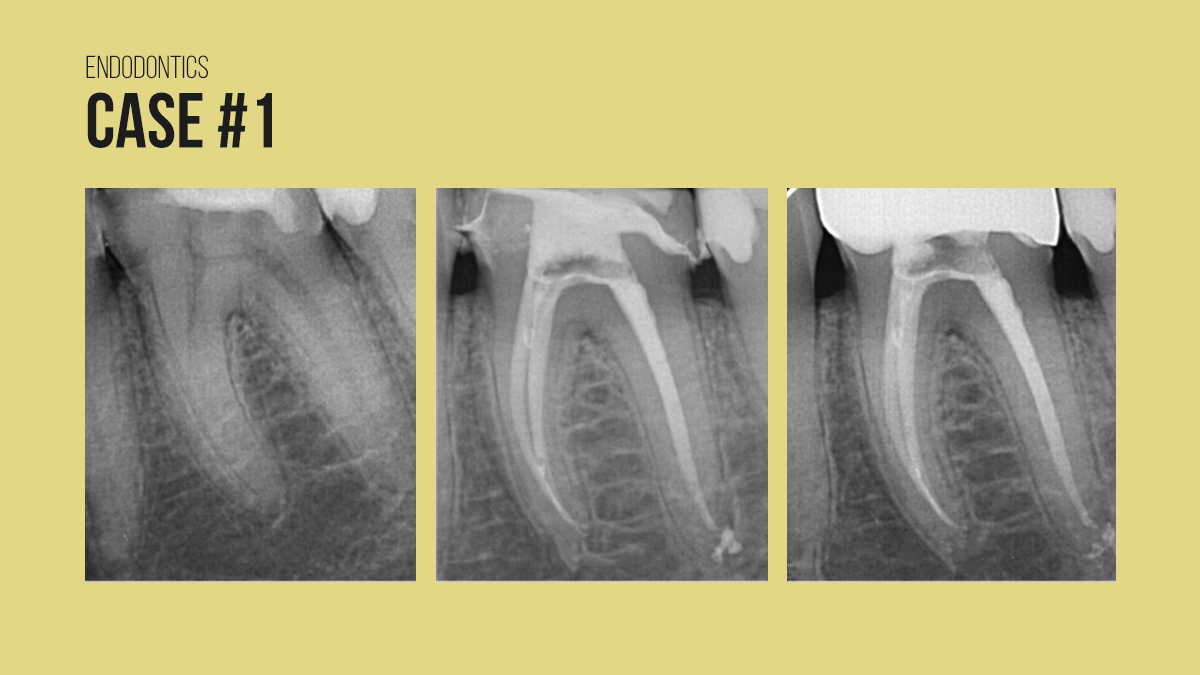

علاج جذور الأسنان: هو اجراء يهدف الى إنقاذ السن الذي تضرر لبه وهو النسيج الرخو الموجود داخل السن الذي يحتوي على الأعصاب والأوعية الدموية يحدث الضرر عادة بسبب التسوس العميق أو الاصابة أو الكسور